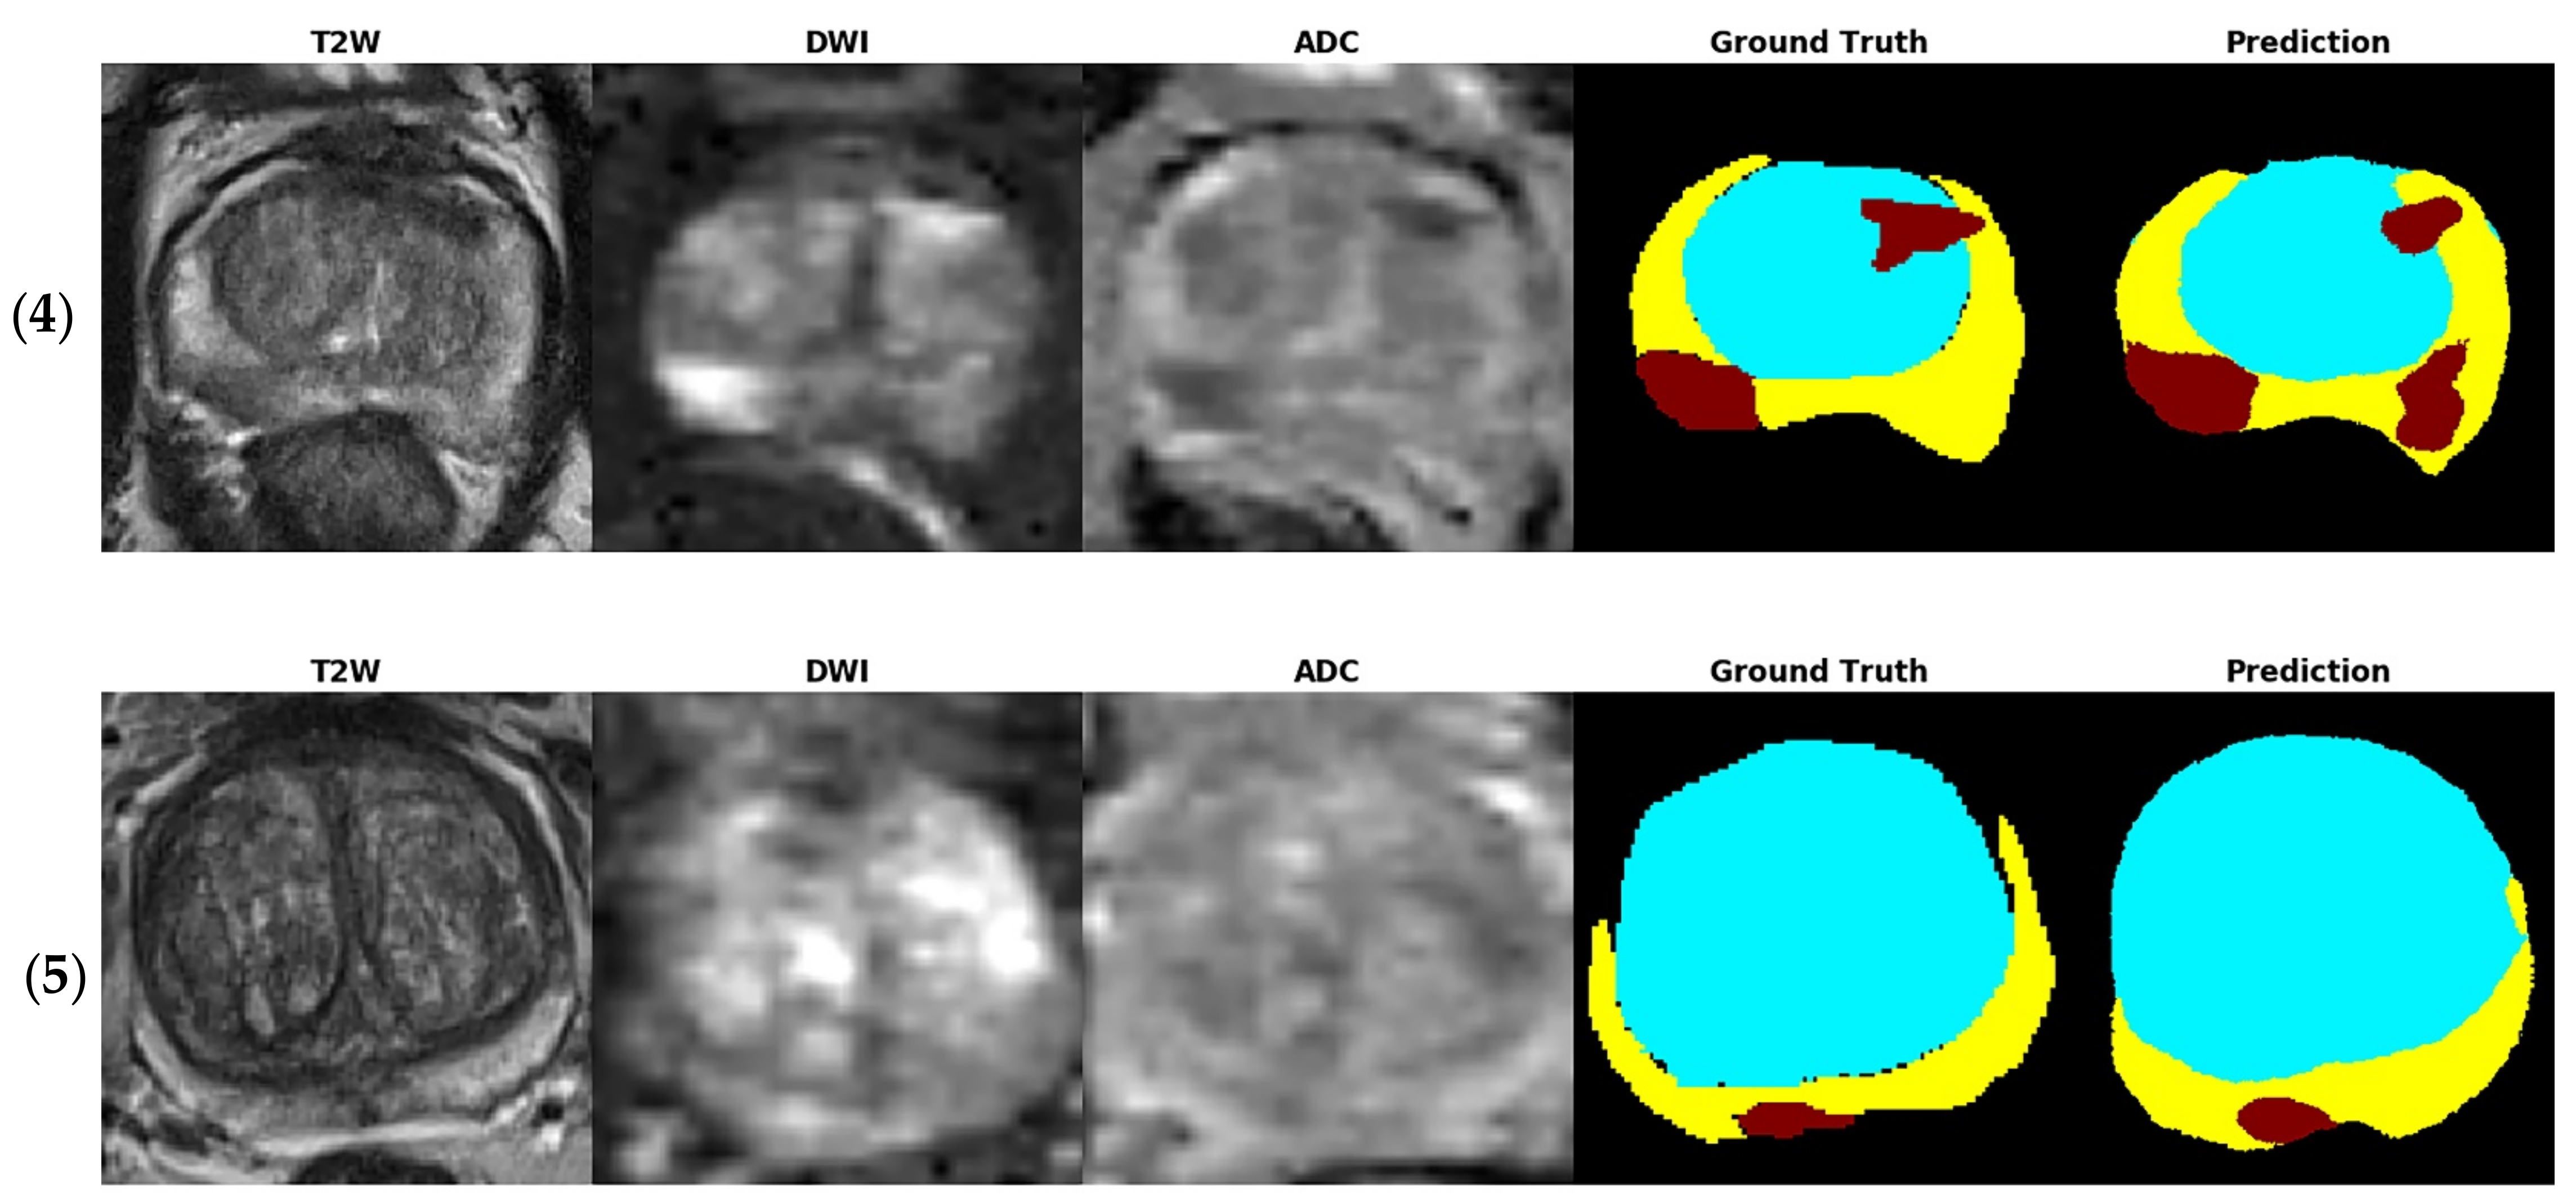

Figure 4 shows several examples of test images in the T2W image + DWI + ADC image model. The ground truth images of segmentation and the corresponding prediction results are illustrated in the aforementioned figure. The TZ in the prediction image was generally similar to that in the ground truth image. The PZ region generally was in the correct location, with considerable discordance at the boundary between true labeled image and predict image. The true PCa regions were observed in the prediction images, and FP predictions were common, especially in the PZ (9% to 12%), as indicated in the confusion matrix in Figure 3. By inspecting the original MRI images, we speculate that these FP regions were mainly formed due to the inflammation process. Moreover, in contrast to the label images, the PCa regions were usually underestimated in the prediction images, which may explain the high number of FNs of PCa in the PZ (23–39%).

Figure 4. Test images of five patients (15) in the T2W image + DWI + ADC image model. The tumor location was provided from dataset. The ground truth images of segmentation and the corresponding prediction results are illustrated (blue region: TZ, yellow region: PZ, and red region: PCa).